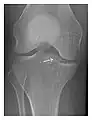

High-energy trauma fractures

Occult osseous injuries may result from a direct blow to the bone by compressive forces of adjacent bones against one another or by traction forces during an avulsion injury. Lesions in the tibial plateau, hip, ankle, and wrist are often missed. In a tibial plateau fracture, any disruption of the posterior and anterior cortical rims of the plateau should be sought. Impaction of subchondral bone will appear as an increased sclerosis of the subchondral bone (Figure 1). In the hip, posterior acetabular fractures also present subtle radiographic findings. The acetabular lines should then be carefully examined keeping in mind that the posterior rim, which is harder to see on X-rays, is more frequently fractured than the anterior rim (Figure 2). In the wrist, detection of carpal bone fractures is often challenging, with up to 18% of scaphoid fractures radiographically occult. Carpal fractures, especially the scaphoid, are associated with the risk of avascular necrosis. In apparently normal wrist radiographs from symptomatic patients, if there is history of a fall on an outstretched hand with pain in the anatomic snuffbox, suggesting scaphoid injury, the initial examination with posteroanterior, lateral, and pronation oblique views must be complemented by other specific views such as supination oblique and the "scaphoid" view A careful examination of cortices for evidence of discontinuity or offset and cancellous bone for lucency is necessary (Figure 3).[1]

a

b

c

Figure 3: A 26-year-old man presenting with wrist pain after being assaulted. (a) Initial anteroposterior radiograph shows a subtle linear lucency within the scaphoid extending to the scaphocapitate articular surface that was overlooked (arrow). (b) Initial "scaphoid" view was negative. (c) Followup anteroposterior radiographs, 12 days later, shows obvious scaphoid fracture (arrows).[1]